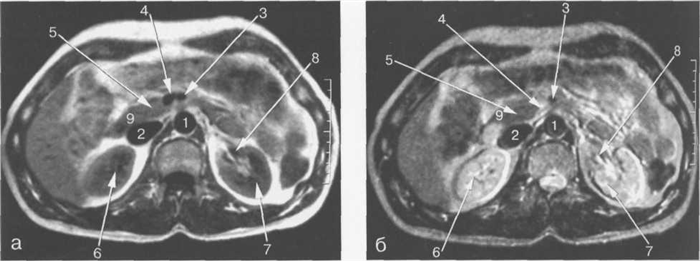

Рис. 11.13. МРТ брюшной полости в аксиальной плоскости на уровне внутрипеченочных ветвей воротной вены.

1 — аорта; 2 — нижняя полая вена; 3 — селезеночная вена; 4 — тело поджелудочной железы; 5 — желудок; 6 — селезенка; 7 — левый надпочечник; 8 — правый надпочечник; 9 — задние сегменты ветви правой воротной вены; 10 — медиальные сегменты левой доли печени; 11 — верхний полюс левой почки.

Рис. 11.14. МРТ брюшной полости на уровне ворот селезенки.

1 — аорта; 2 — нижняя полая вена; 3 — левая желудочная артерия; 4 — селезеночная артерия; 5 — желудок; 6 — селезенка; 7 — толстая кишка; 8 — хвост поджелудочной железы.

Рис. 11.15. МРТ брюшной полости в аксиальной плоскости на уровне желчного пузыря.

1 — аорта; 2 — нижняя полая вена; 3 — селезеночная вена; 4 — верхняя брыжеечная артерия; 5 — желчный пузырь; 6 — левый надпочечник; 7 — правый надпочечник; 8 — левая почка; 9 — кортикальный слой левой почки.

Рис. 11.16. MPT брюшной полости в аксиальной плоскости на уровне головки поджелудочной железы.

1 — аорта; 2 — нижняя полая вена; 3 — верхняя брыжеечная артерия; 4 — верхняя брыжеечная вена; 5 -головка поджелудочной железы; 6 — верхний полюс правой почки; 7 — левая почка; 8 — левая почечная артерия; 9 — общий желчный проток.